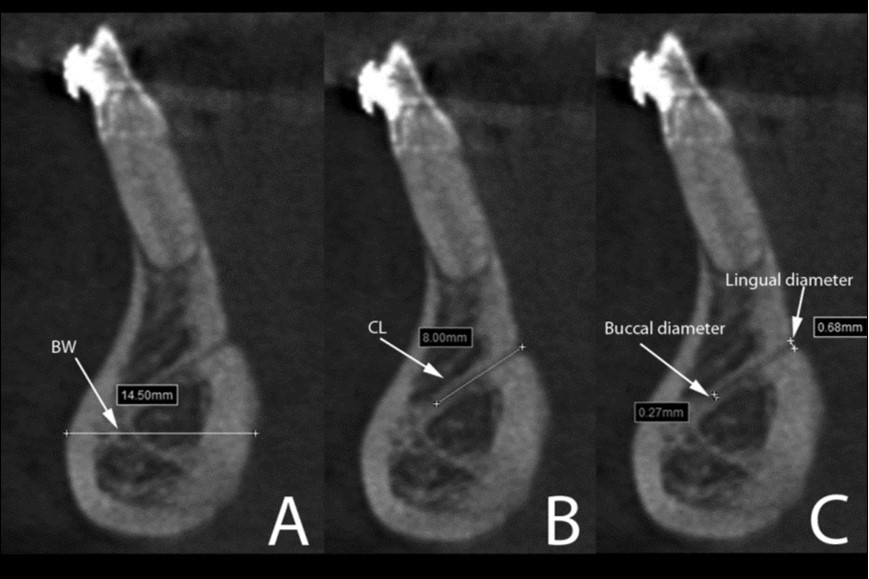

Human, Chimpanzee and Gorilla groups showed significant differences in the dimensions of the mandibular canal, mental foramen, incisive canal, lingual canal and in the anterior mandibular bone width (Figure 4). The Gorilla group showed significant higher medians for the mandibular canal, lingual canal length and bone width than Human and Chimpanzee groups (Table 1).

Figure 4.Cross-sectional views show the lingual canal. Images (A), (B) and (C) show the measurement of bone width (BW, the longest distance in the anterior mandibles under the lingual canal), canal length (CL) and lingual canal diameter (buccal and lingual), respectively.

Cross-sectional views show the lingual canal. Images (A), (B) and (C) show the measurement of bone width (BW, the longest distance in the anterior mandibles under the lingual canal), canal length (CL) and lingual canal diameter (buccal and lingual), respectively.

On the other hand, human mandibles showed significant larger range of mental foramen (3.3mm/2.7-4.0mm) compared to Chimpanzee (2.1mm/1.7-2.7mm) and Gorilla (2.1mm/1.9-2.9mm). No incisive canal could be observed in the Gorilla group, while very few were presented in Chimpanzee. The incisive canal diameter was significantly larger in Human (IC/start: 1.9mm/1.6-2.6mm) than in Chimpanzee (IC/start: 0.9mm/0.8-1.1mm). For the root lengths, the longest third molar was observed in the Gorilla group (13mm/10.1-14.8mm), whereas the Human group presented the longest second premolar (14.5mm/13.4-16.4mm) and Chimpanzee showed the longest canine (18.1mm/15.4-21.9mm).